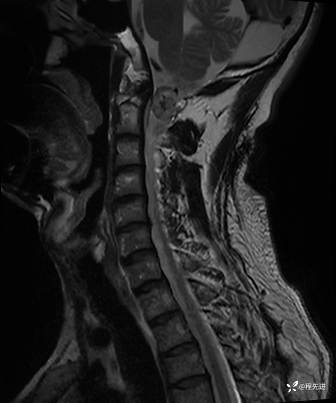

MRI平扫+增强:

T2: